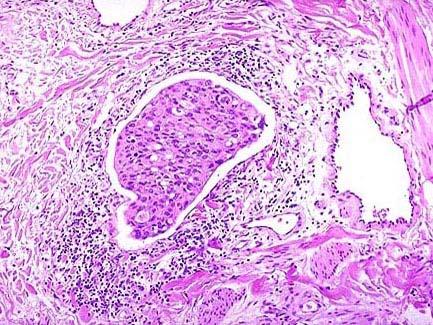

问题 死者,男性,65岁,晚期胃癌术后2年突发呕血而亡。尸检见两肺表面遍布直径0.5cm至直径1.5cm大小灰黄色结节,如图所示,该患者最可能的诊断是 ( )

选项 A.硅肺 B.粟粒性肺结核 C.肺鳞状细胞癌 D.细支气管肺泡癌 E.肺转移癌

答案 E